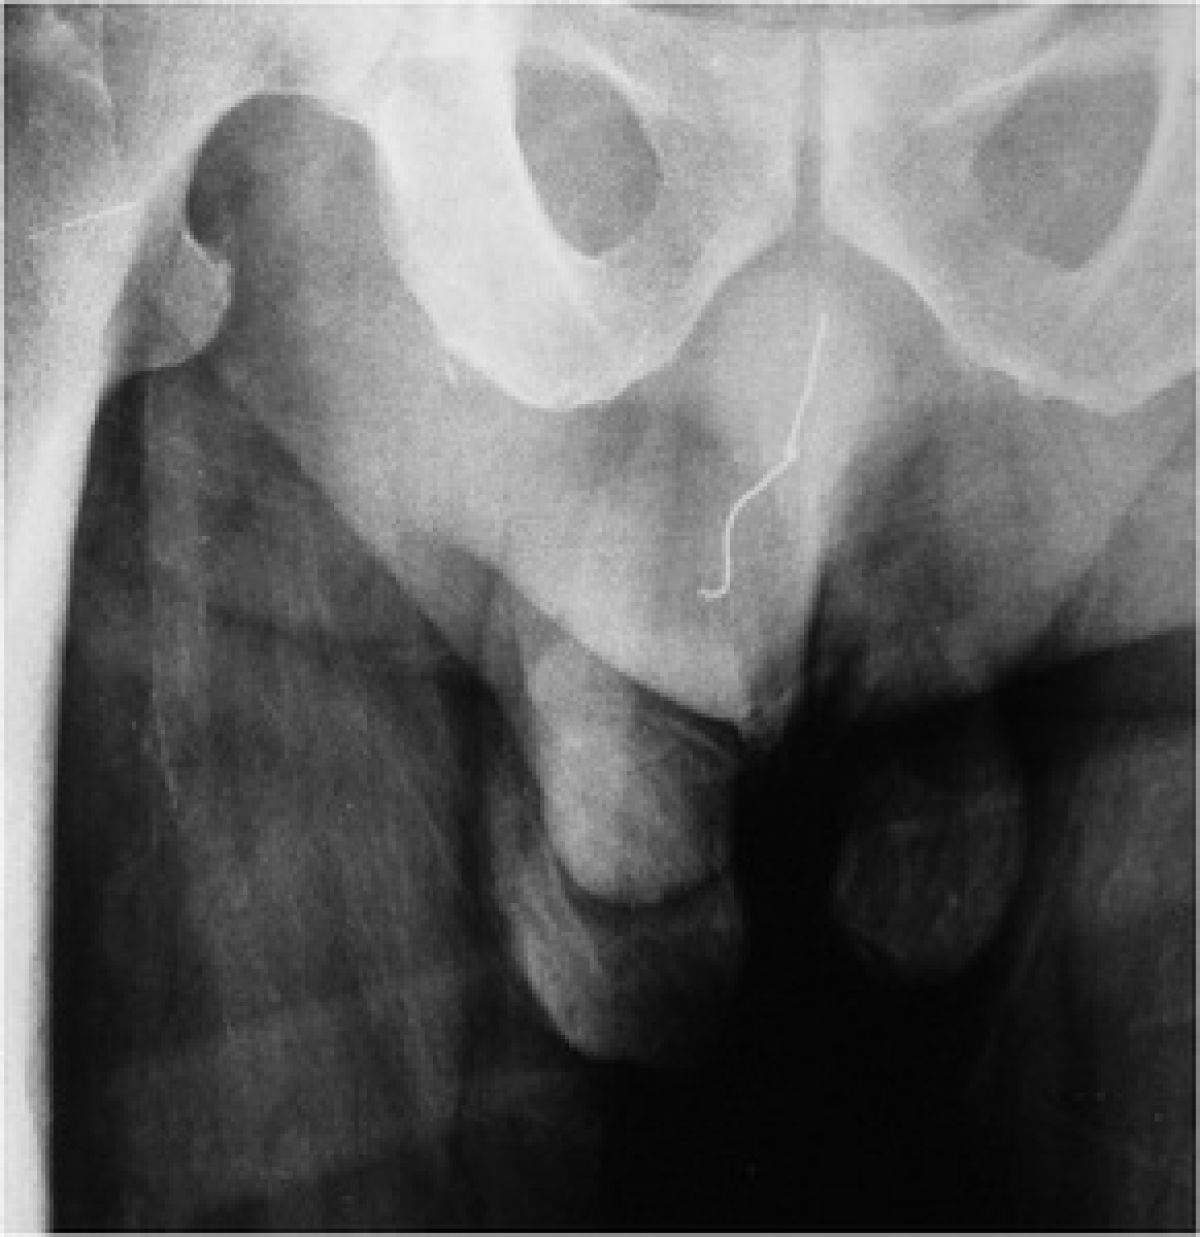

32-letni moški je poiskal pomoč na urgenci zaradi bolečin v penisu. Zdravnike je pričakalo precejšnje presenečenje ...

32-letni Kitajec je prišel na urgentni oddelek bolnišnice Shenzhen Shuguang na Kitajskem zaradi infekcije penisa. A zdravnikom je 'pozabil' povedati, da si je vanj vstavil kabel za slušalke. Tega naj ne bi storil zaradi spolnih užitkov, temveč naj bi verjel, da se tako lahko sam pozdravi. Da naj bi mu vstavljanje kabla pomagalo premagati bolečino, naj bi mu svetoval prijatelj. Kot so povedali zdravniki, je 32-letnik zaradi tega le utrpel še hujšo infekcijo.

Zdravniki so med 20-minutno operacijo iz penisa izvlekli kar 45 centimetrov dolg kabel za slušalke. Dr. Xu Chang, ki je operiral32-letnika, zdaj opozarja vse moške, naj si v primeru bolečin v predelu sečil nikakor ne tlačijo nobenih predmetov v penis, saj lahko na ta način povzročijo še hujše infekcije.